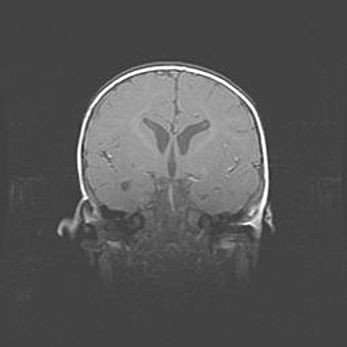

Открытая гидроцефалия.

Возраст: 9 месяцев 12 дней

Вес: 6800 г

Пол: мужской

Окружность головы: 41,5 см

Срок гестации: 28 недель

Гидроцефалия головного мозга у новорожденных имеет характерный признак: опережающий рост окружности головы приводит к визуально хорошо определяемой гидроцефальной форме сильно увеличенного в объёме черепа. Детские неврологи определяют следующие симптомы гидроцефалии у грудничков: выбухающий напряжённый родничок, частое запрокидывание головы, смещение глазных яблок к низу.